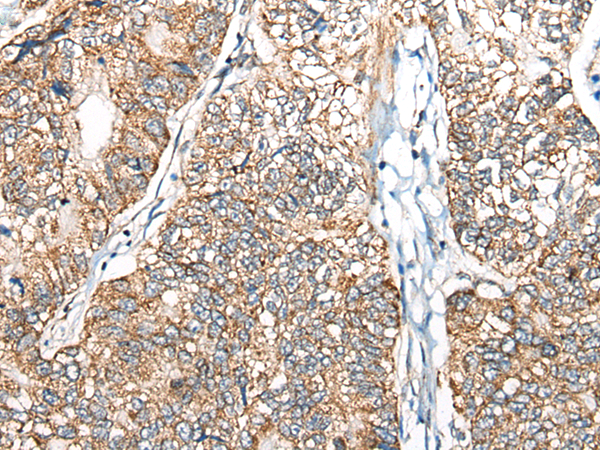

中文名稱: 兔抗NADK2多克隆抗體

英文名稱: Anti-NADK2 rabbit polyclonal antibody

別       名: NAD kinase 2, mitochondrial; DECRD; MNADK; NADKD1; C5orf33

This gene encodes a mitochondrial kinase that catalyzes the phosphorylation of NAD to yield NADP. Mutations in this gene result in 2,4-dienoyl-CoA reductase deficiency. Alternative splicing results in multiple transcript variants.

Applications:

ELISA, WB

Fusion protein of human NADK2

NAD kinase 2, mitochondrial

WB Positive control:

HEPG2, Hela and A549 cell lysates